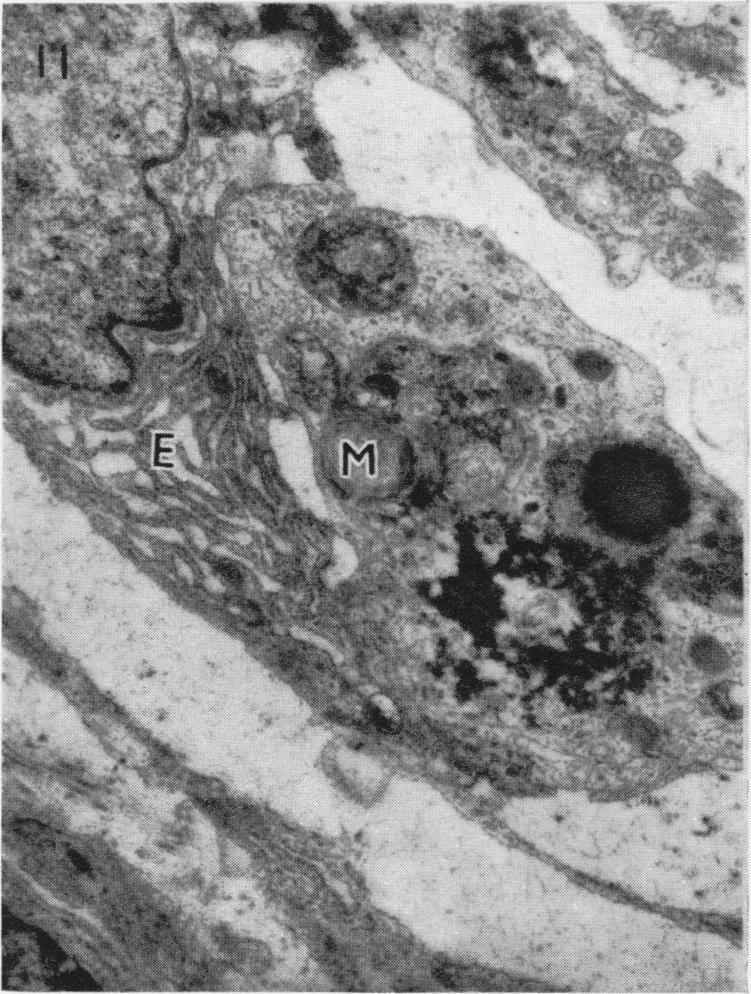

AN ELECTRON MICROSCOPE STUDY OF HUMAN BREAST CELLS IN FIBROADENOSIS AND CARCINOMA.

Br J Cancer. 1964 Dec;18(4):682-5. doi: 10.1038/bjc.1964.78.